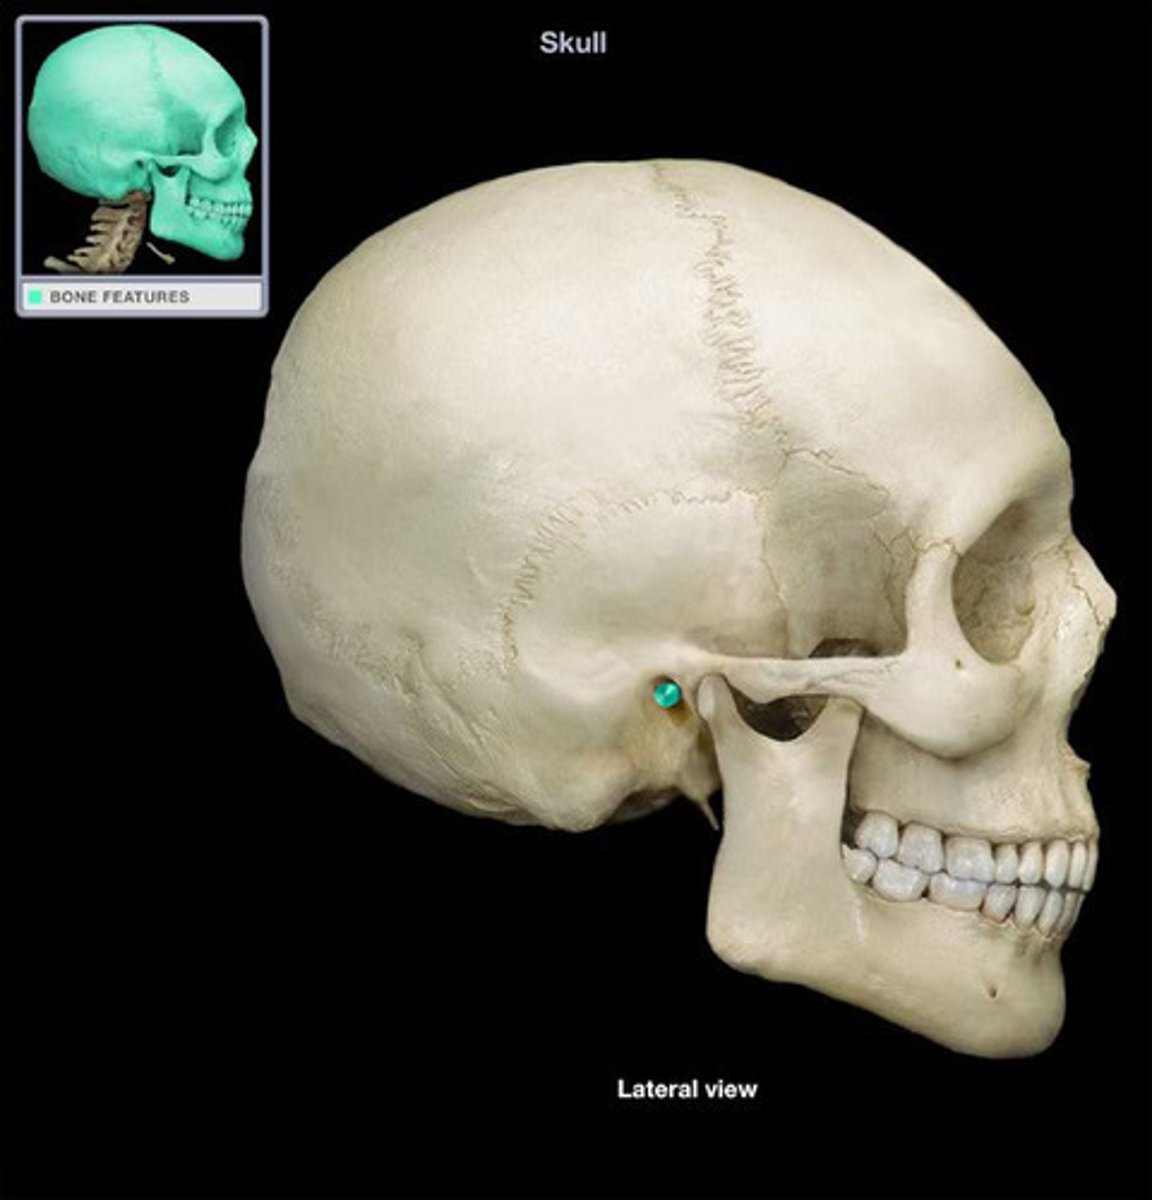

Frontal Bone

Parietal Bone

Parietal Bone

Occipital Bone

Temporal Bone

Temporal Bone

Zygomatic arch

Mastoid Process

Mastoid Process

External Auditory Meatus

External Auditory Meatus

Mandibular Fossa

Styloid Process

Stylomastoid Foramen